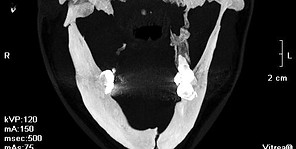

ПІДВИЩЕННЯ КВАЛІФІКАЦІЇ В ЩЕЛЕПНО-ЛИЦЕВІЙ ХІРУРГІЇ І ХІРУРГІЧНІЙ СТОМАТОЛОГІЇ